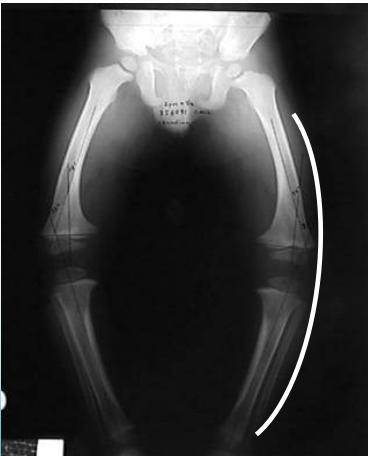

Radiological Assessment

Indications: X-ray when severe or possibly pathologic

Recommended Views:

- Standing AP film: Long film (hips to ankles) with patellae directed forwards

Radiological Parameters to Assess:

- Medial Physeal Slope

- Femoral-Tibial Axis

Conditions to Look For:

Rickets

Tibia vara (Blount’s disease)

Epiphyseal injury

Angle measurements

Medial Physeal Slope

Femoral-Tibial Axis